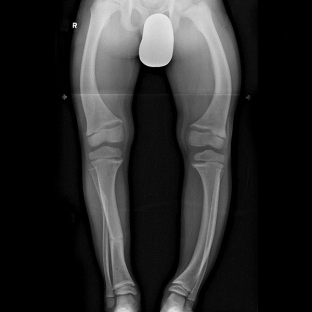

Інструмент Дослідження також широко застосовуються для діагностики синдрому остеомаляції. За допомогою гістоморфологічного дослідження вдається оцінити швидкість кальцифікації та кісткоутворення. Для цього застосовується метод подвійної тетрациклінової мітки, за результатами якого при остеомаляції зменшується відстань. між двома тетрацикліновими мітками, і з'являється немінералізований матрикс. Рентгенологічні дослідження є найінформативнішими при синдромі остеомаляції. Важливими ознаками остеомаляції є зміни тіл хребців: розмитість їх малюнків, увігнутість країв,

Характерним рентгенологічним симптомом остеомаляції є виявлення зон Лоозера – тріщин або вузьких ліній, які пропускають рентгенівські промені, мають склеротично змінені краї та розташовуються перпендикулярно кортикальному краю кістки.